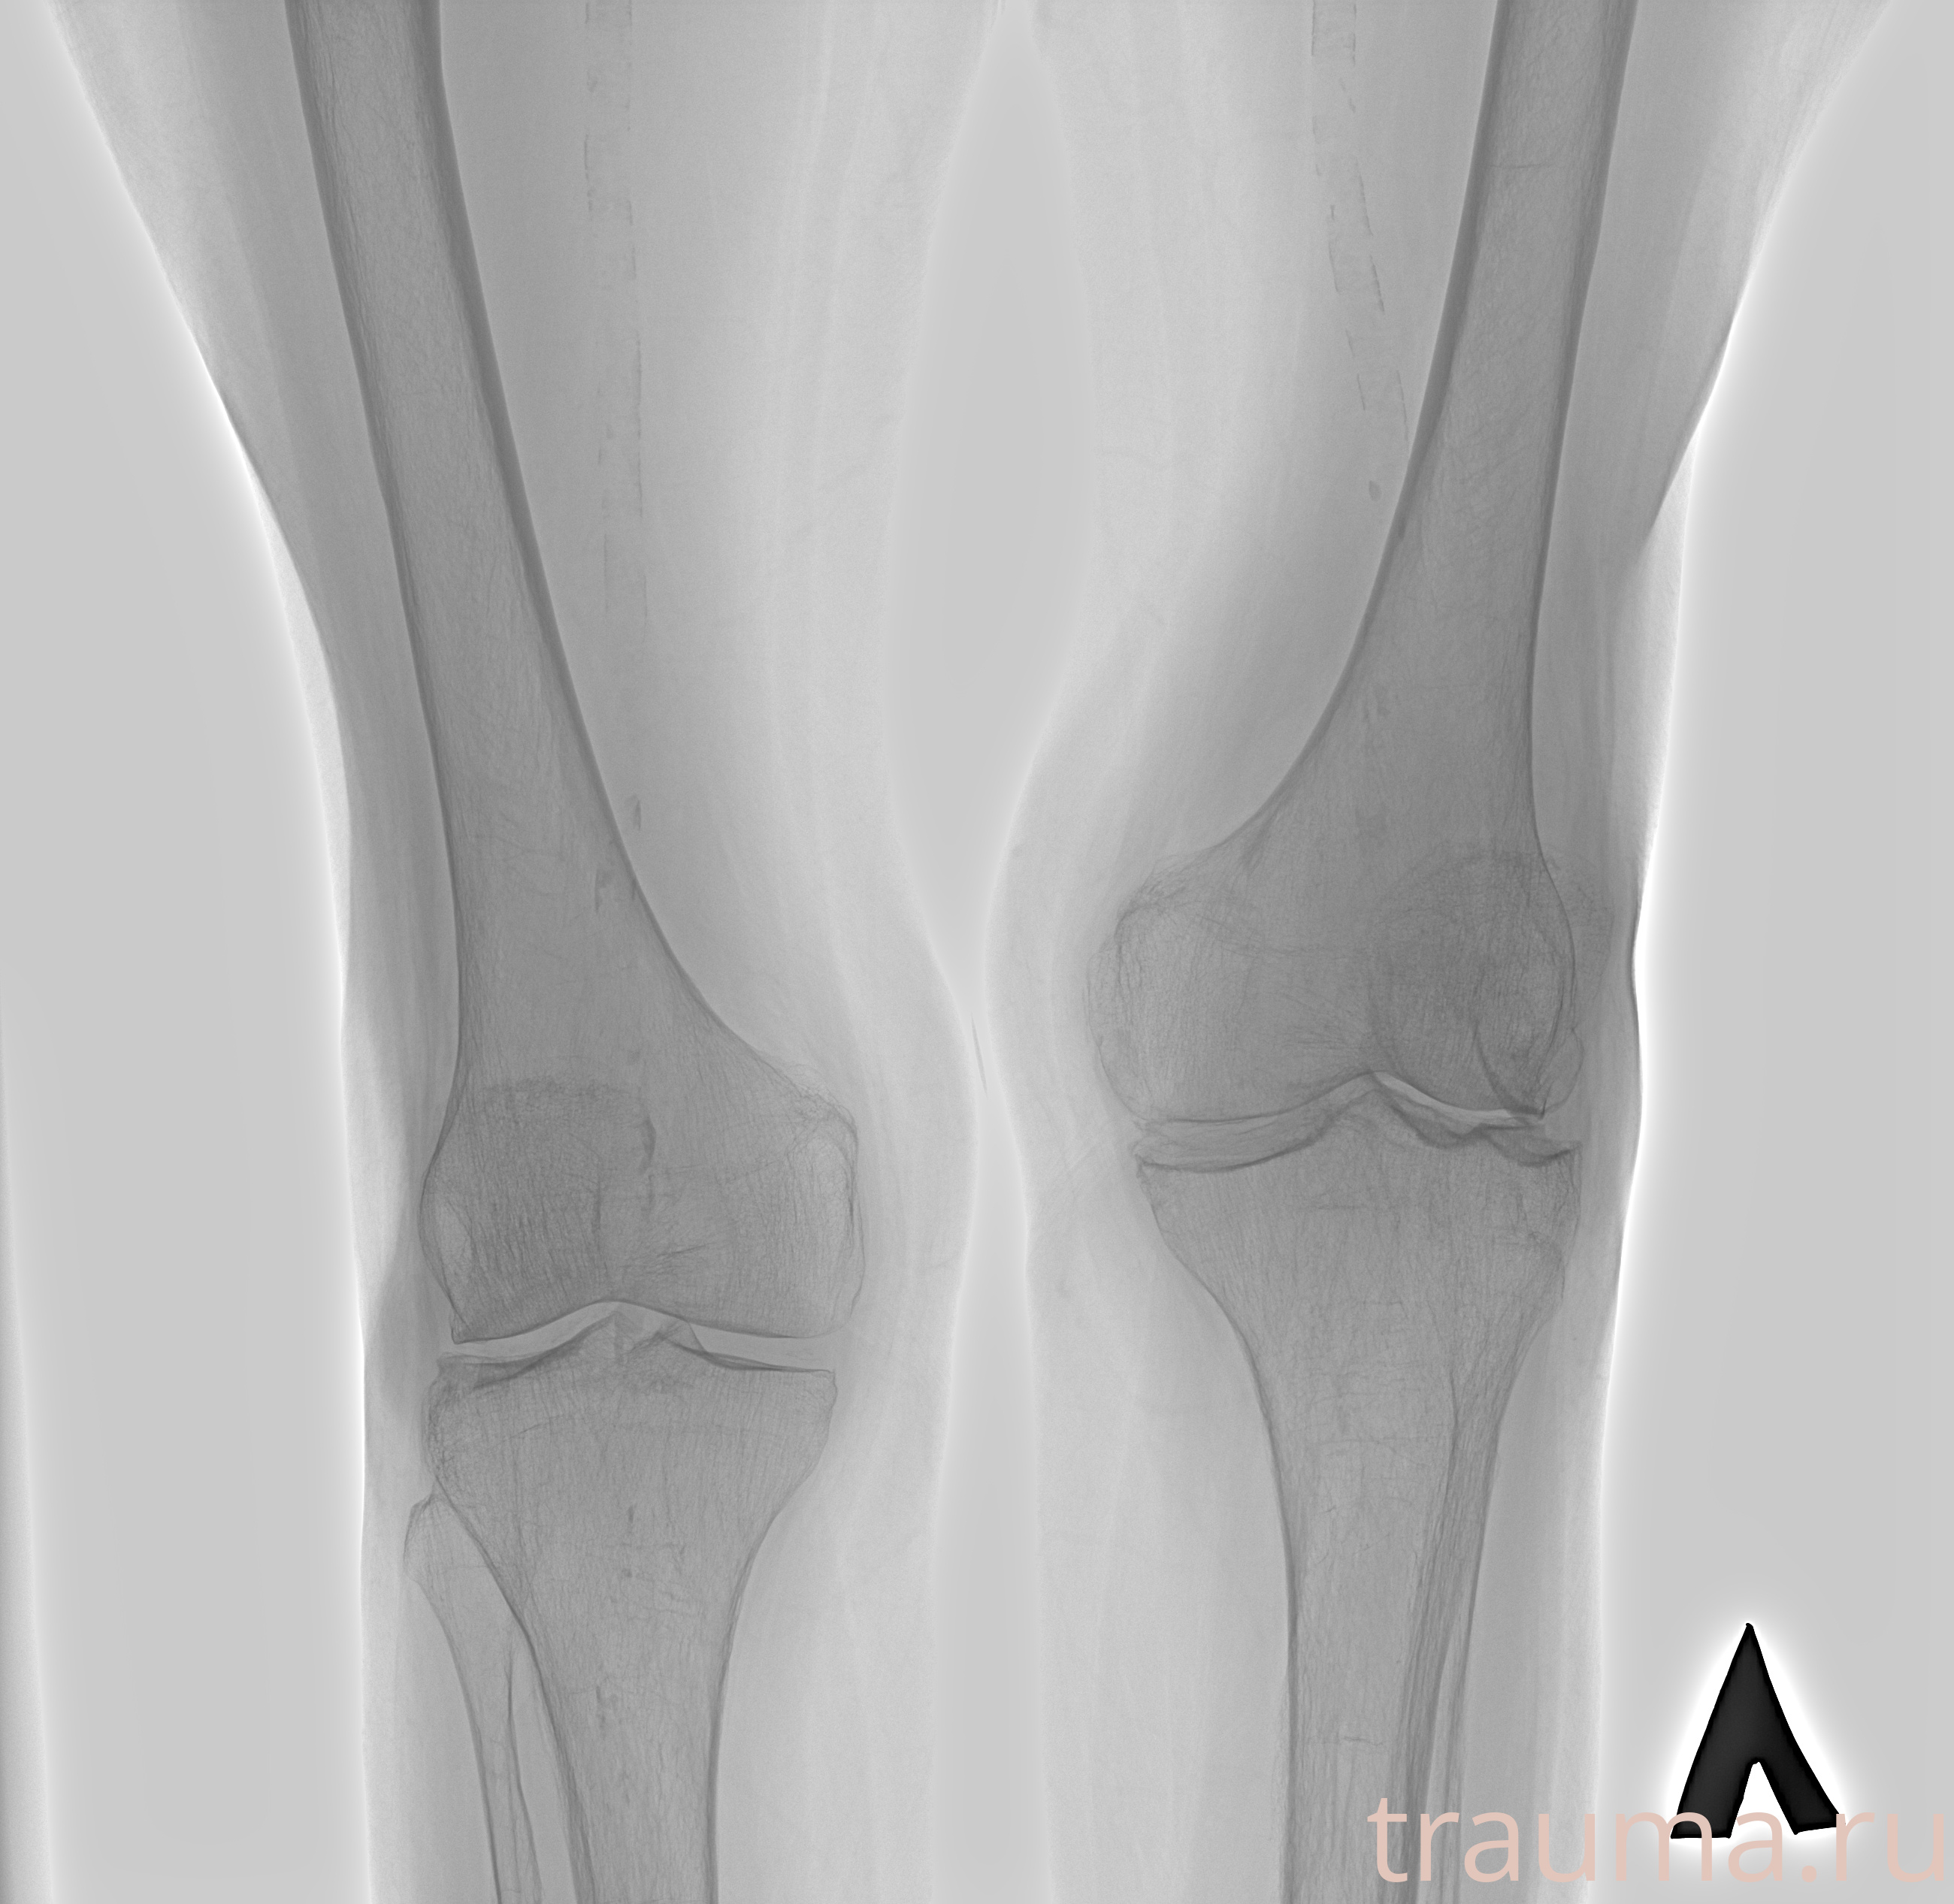

Рентген на дому: по вашему адресу приезжает врач-рентгенолог, травматолог-ортопед с мобильным рентгеновским аппаратом, проводит диагностику травмы или заболевания, делает необходимые рентгенограммы, дает рекомендации по дальнейшему лечению. Получить качественные снимки в домашних условиях возможно благодаря уникальной методике, разработанной МосРентген Центром для института  Склифосовского